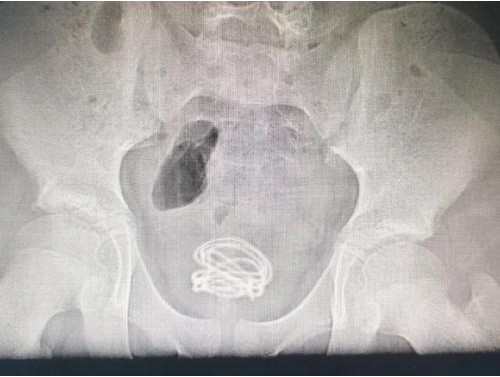

袁浩锋立即安排小何做X光检查,X光片上可以清晰看到小何的膀胱中有一团线圈,需要手术取出。

袁浩锋随后安排小何住院,经过术前准备,第二天为他实施了“膀胱镜经尿道异物取出术”。

术中,一根长达70厘米的富有弹性的塑料软电线被取出,表面附着尿垢和硬化晶体,很粗糙,主刀医生蔡崇岳医生感慨:“真没想到这么长的电线都能从尿道塞进去,幸好电线没有在膀胱中造成二次伤害。”